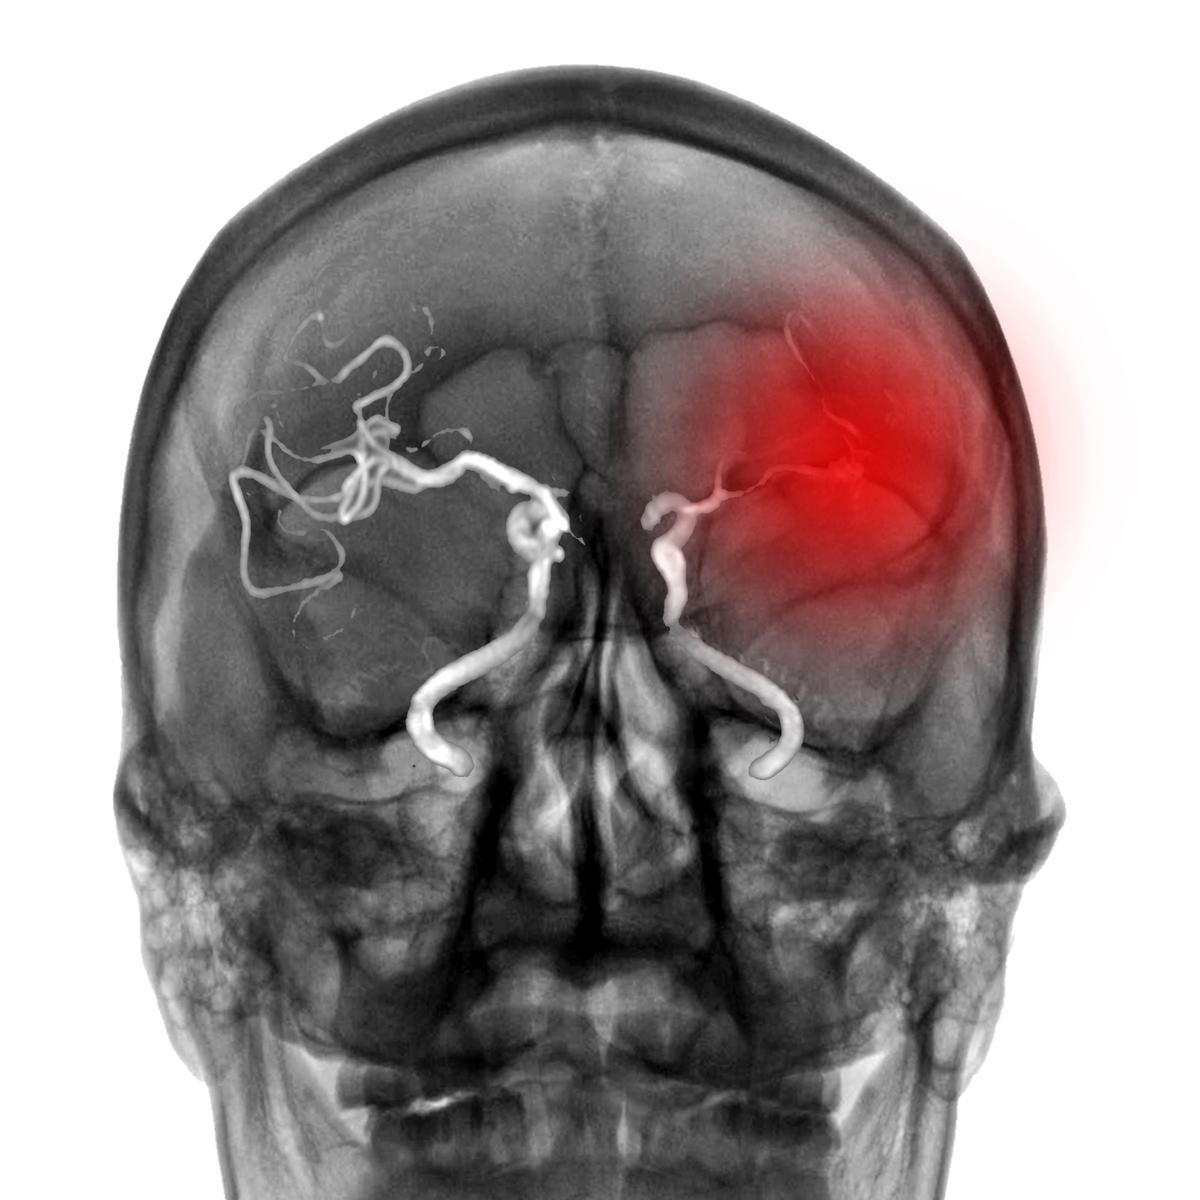

Όταν με έβαλαν στον αξονικό τομογράφο, φάνηκε ένα μεγάλο αιμάτωμα στο αριστερό μπροστά κομμάτι του εγκεφάλου μου. Να σημειώσω εδώ ότι είχα συνεχόμενες κρίσεις και στην αξονική, μολονότι μου είχαν χορηγήσει δυο ηρεμιστικές ενέσεις.

Οι εξετάσεις έδειξαν εγκεφαλική αιμορραγία η οποία, όπως μου είπαν, δεν είχε παθολογική αιτία. Προέκυψε από τα συνεχόμενα επιληπτικά επεισόδια.

Ενόσω ήταν σε εξέλιξη οι εξετάσεις μου, ο νευροχειρουργός είπε στη σύζυγο μου πως ενδέχεται να μην μπορέσω να ξαναμιλήσω ή να ξαναπερπατήσω, καθώς το αιμάτωμα ήταν στο σημείο του εγκεφάλου που ελέγχει την κίνηση και την ομιλία.